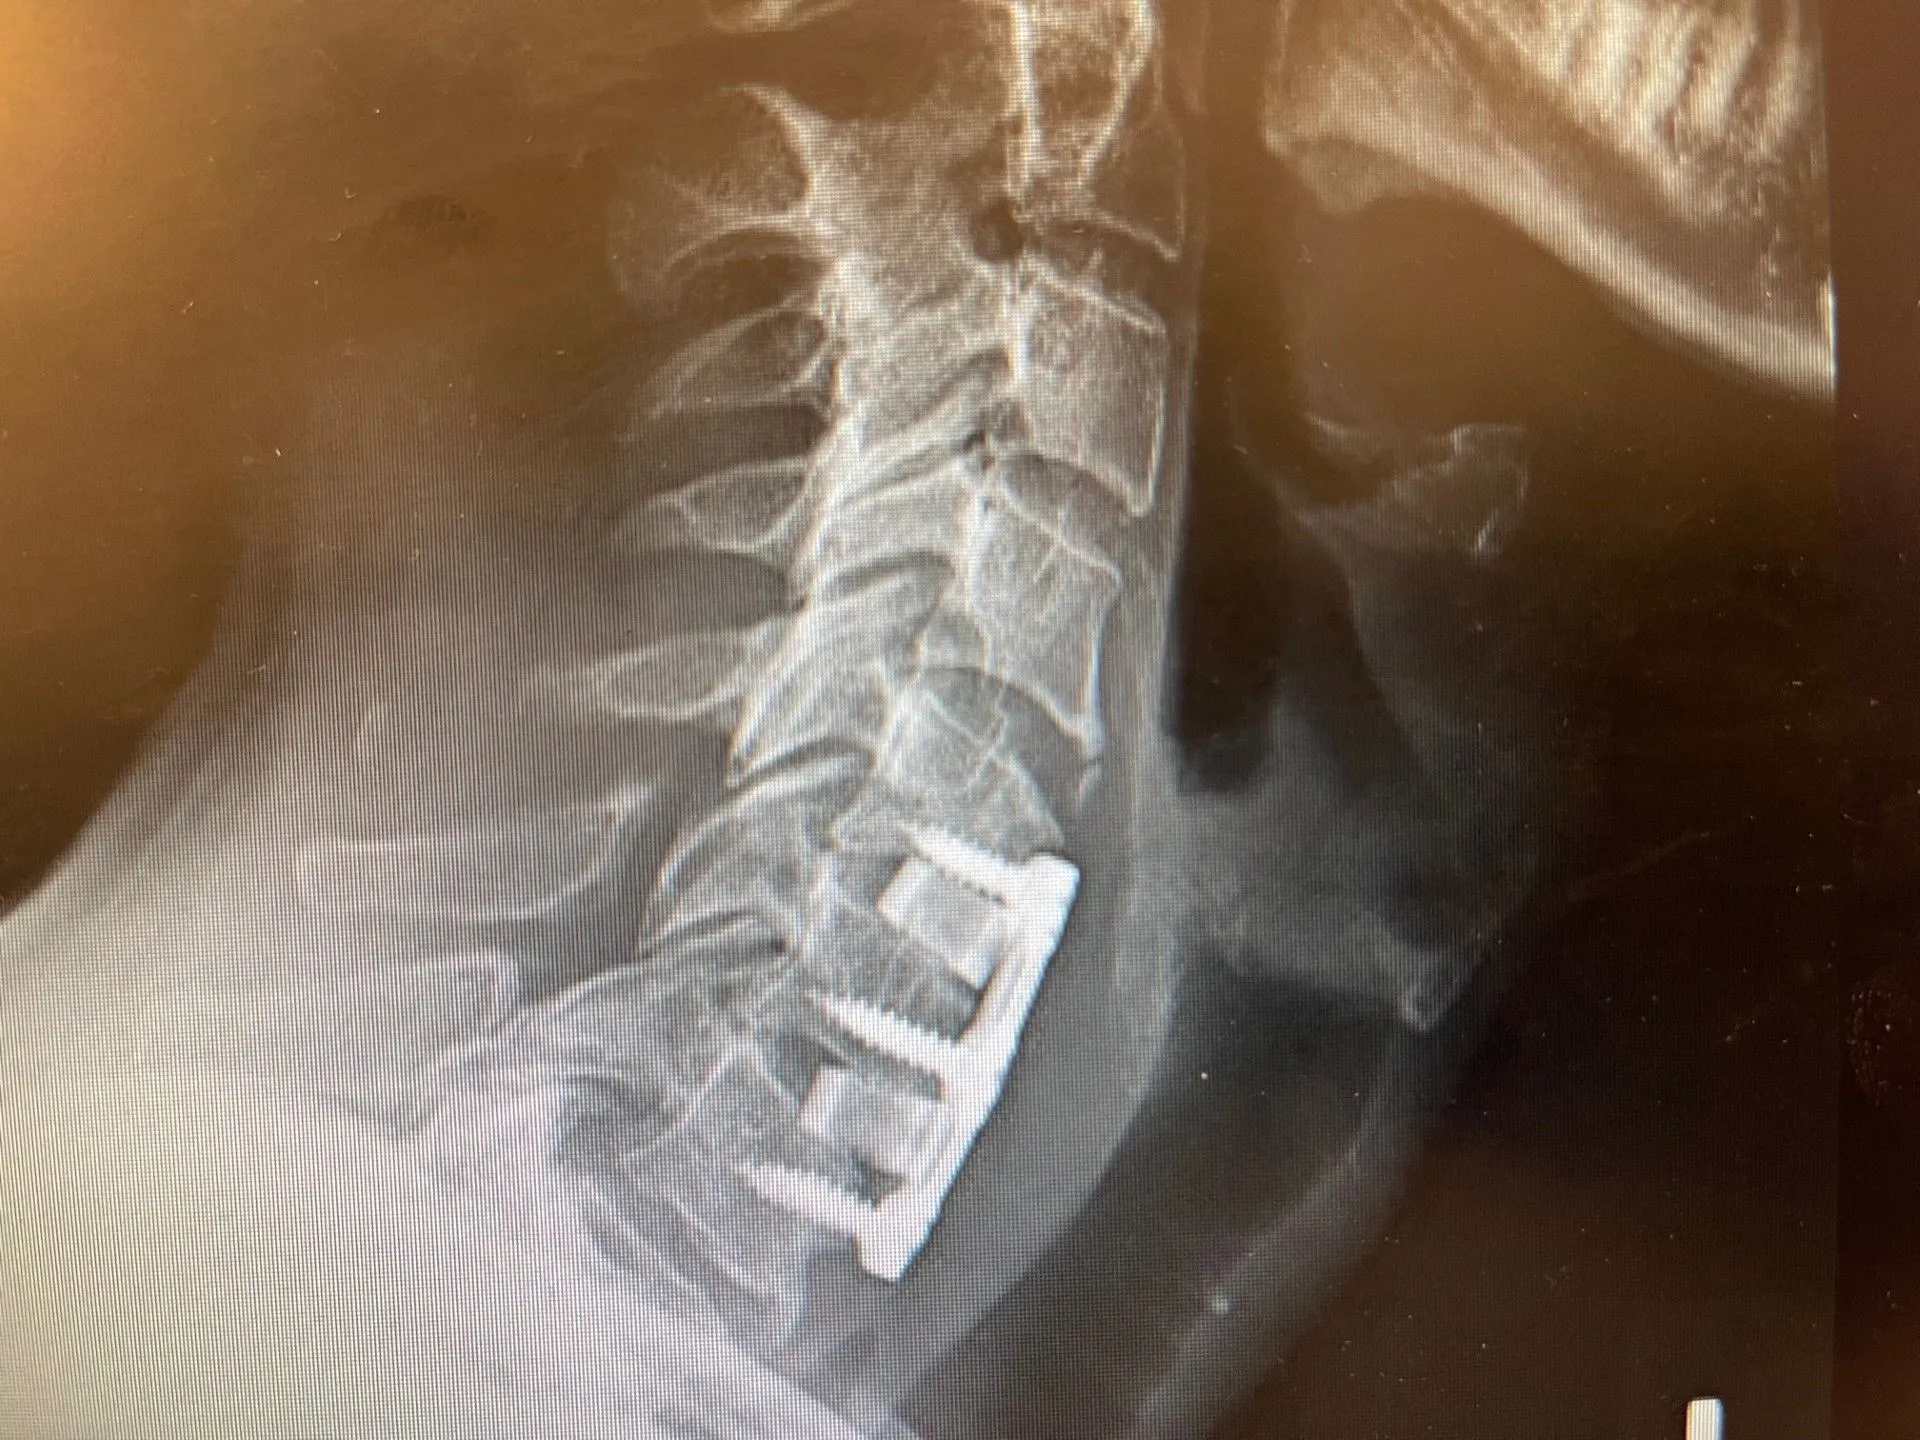

Unlike traditional open cervical surgery, Deuk Laser Disc Repair® is performed through a 4mm opening using an endoscope and a specialized laser. The procedure directly targets the source of nerve compression by treating the damaged disc tissue and eliminating the inflammation that is irritating the nerve root. There is no hardware, no bone grafting, no fusion, and no overnight hospital stay. Most patients walk out of the clinic the same day the procedure is performed.

The procedure is indicated for patients with disc herniations, bulging discs, or related disc pathology confirmed on MRI. Patients with significant bone spur-based stenosis may require evaluation for alternative surgical approaches. A consultation with Dr. Deukmedjian will clarify whether Deuk Laser Disc Repair® is appropriate for your specific anatomy and diagnosis.

Sometimes the best way to understand what a procedure means in practice is to hear from someone who lived it. A military veteran from California arrived at Deuk Spine Institute with herniated discs at C5-6 and C6-7 that had been building for years, the result of a lifetime of physical trauma that began in childhood and intensified through years of military service, parachute jumps, and the sustained weight of wearing Kevlar helmets in the field. By the time he sought treatment, the tingling in his left arm had become constant and debilitating.

He had already done his homework before arriving. Disc replacement was one option, but the idea of implanting a metal prosthetic that was never designed for his spine did not sit well with him. Anterior cervical discectomy and fusion (ACDF) was another, but his own mother had undergone lumbar fusion and suffered significant complications over time. He kept searching until he found Deuk Spine Institute.

Less than 24 hours after undergoing Deuk Laser Disc Repair® for both disc levels, he described a quality of relief he had not experienced in over a decade: “It’s a sort of ease that I haven’t had probably for more than 10 years at least.” The radiating arm pain, the electric tingling, the constant tension that had shadowed his daily life were gone. He walked out of the clinic the same day his procedure was performed, without metal implants, without a hospital stay, and without the movement restrictions that come with fusion.